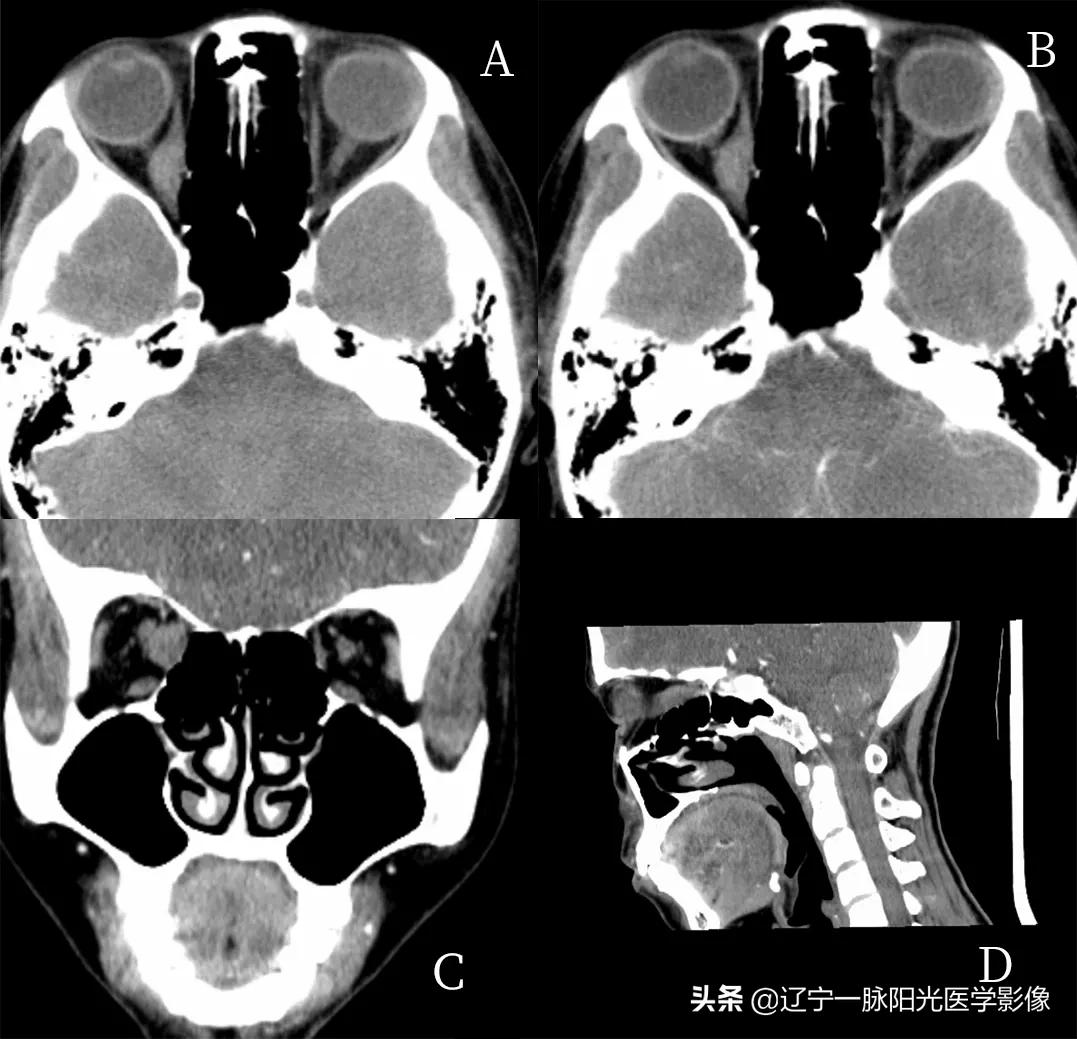

图 A、B、C、D 轴位、冠状位及矢状位示双侧眼球对称性突出,眼肌均匀增厚,以上、下直肌明显,球后脂肪减少

图 A、C、D 双侧球内玻璃体、晶状体密度正常。视神经走行正常,密度均匀,边界清楚

简要病史:女,59 岁,甲状腺功能亢进 5 年,双眼突出半年余